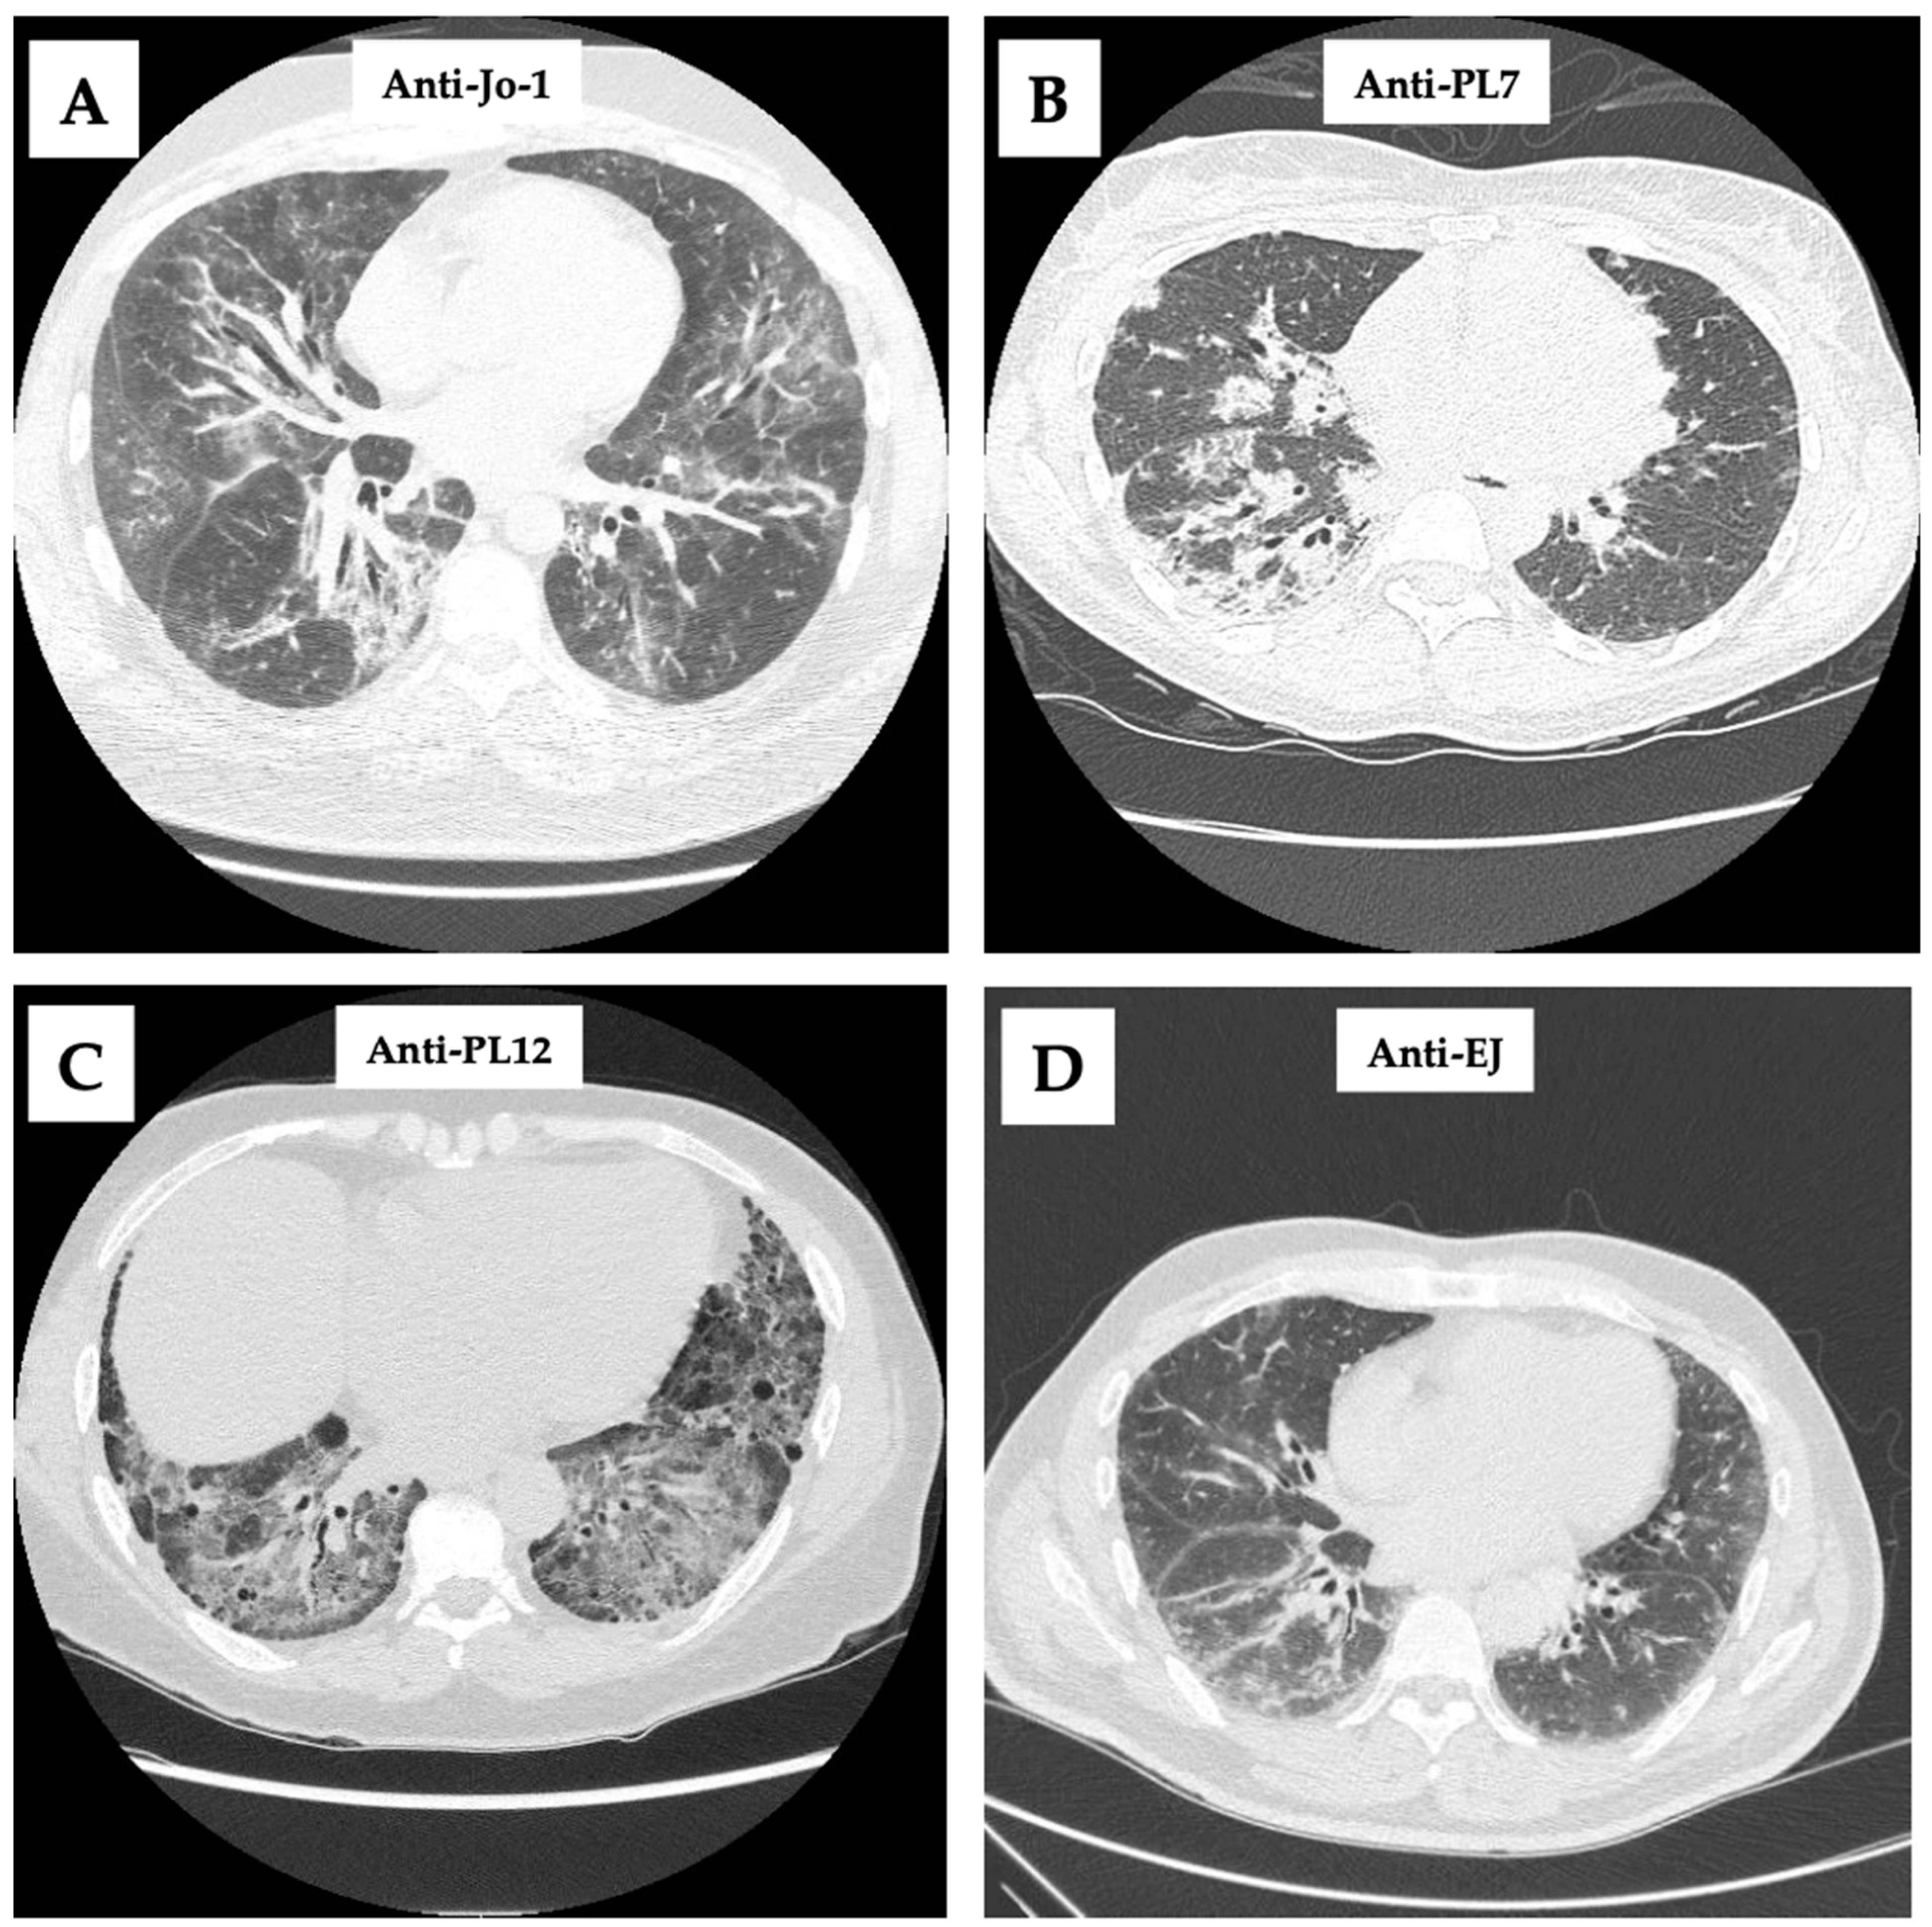

7. Imaging and Histology

- Anti-Jo-1 (Anti-Histidyl tRNA Synthetase)

- Anti-PL7 (Anti-Threonyl tRNA Synthetase) and Anti-PL12 (Anti-Alanyl tRNA Synthetase)

- Anti-EJ (anti-glycyl tRNA synthetase)